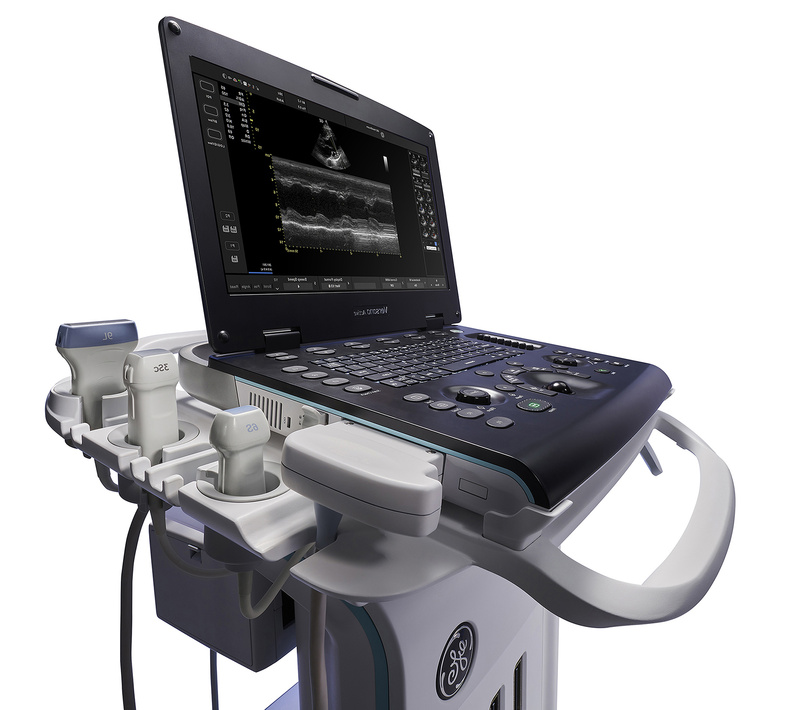

Nasce Versana Active™, il nuovo ecografo portatile interdisciplinare, modulabile e dall’Imaging Quality al top del mercato. Il sistema ad ultrasuoni Versana Active™ garantisce tutta la capacità di imaging di una console in una soluzione leggera e portatile così da poter essere operativi ovunque. Questo efficace ed affidabile sistema unisce la versatilità di un'unità laptop alla possibilità di aggancio a un carrello.

Un’ampia gamma di sonde e funzionalità cliniche consentono di eseguire e analizzare gli esami, da quelli di routine a quelli altamente specialistici in numerosi campi di applicazione clinica.

Sonde per un'ampia gamma di applicazioni

Con le sue ampie funzionalità di imaging e l’efficiente flusso di lavoro, Versana Active™ soddisfa più ambiti clinici e specializzazioni, grazie all‘ampia gamma di sonde disponibili: 8C-RS, 4C-RS, L6-12-RS, 12L-RS, L8-18i-RS, 3Sc-RS, 6S-RS, 12S-RS, LK760-RS